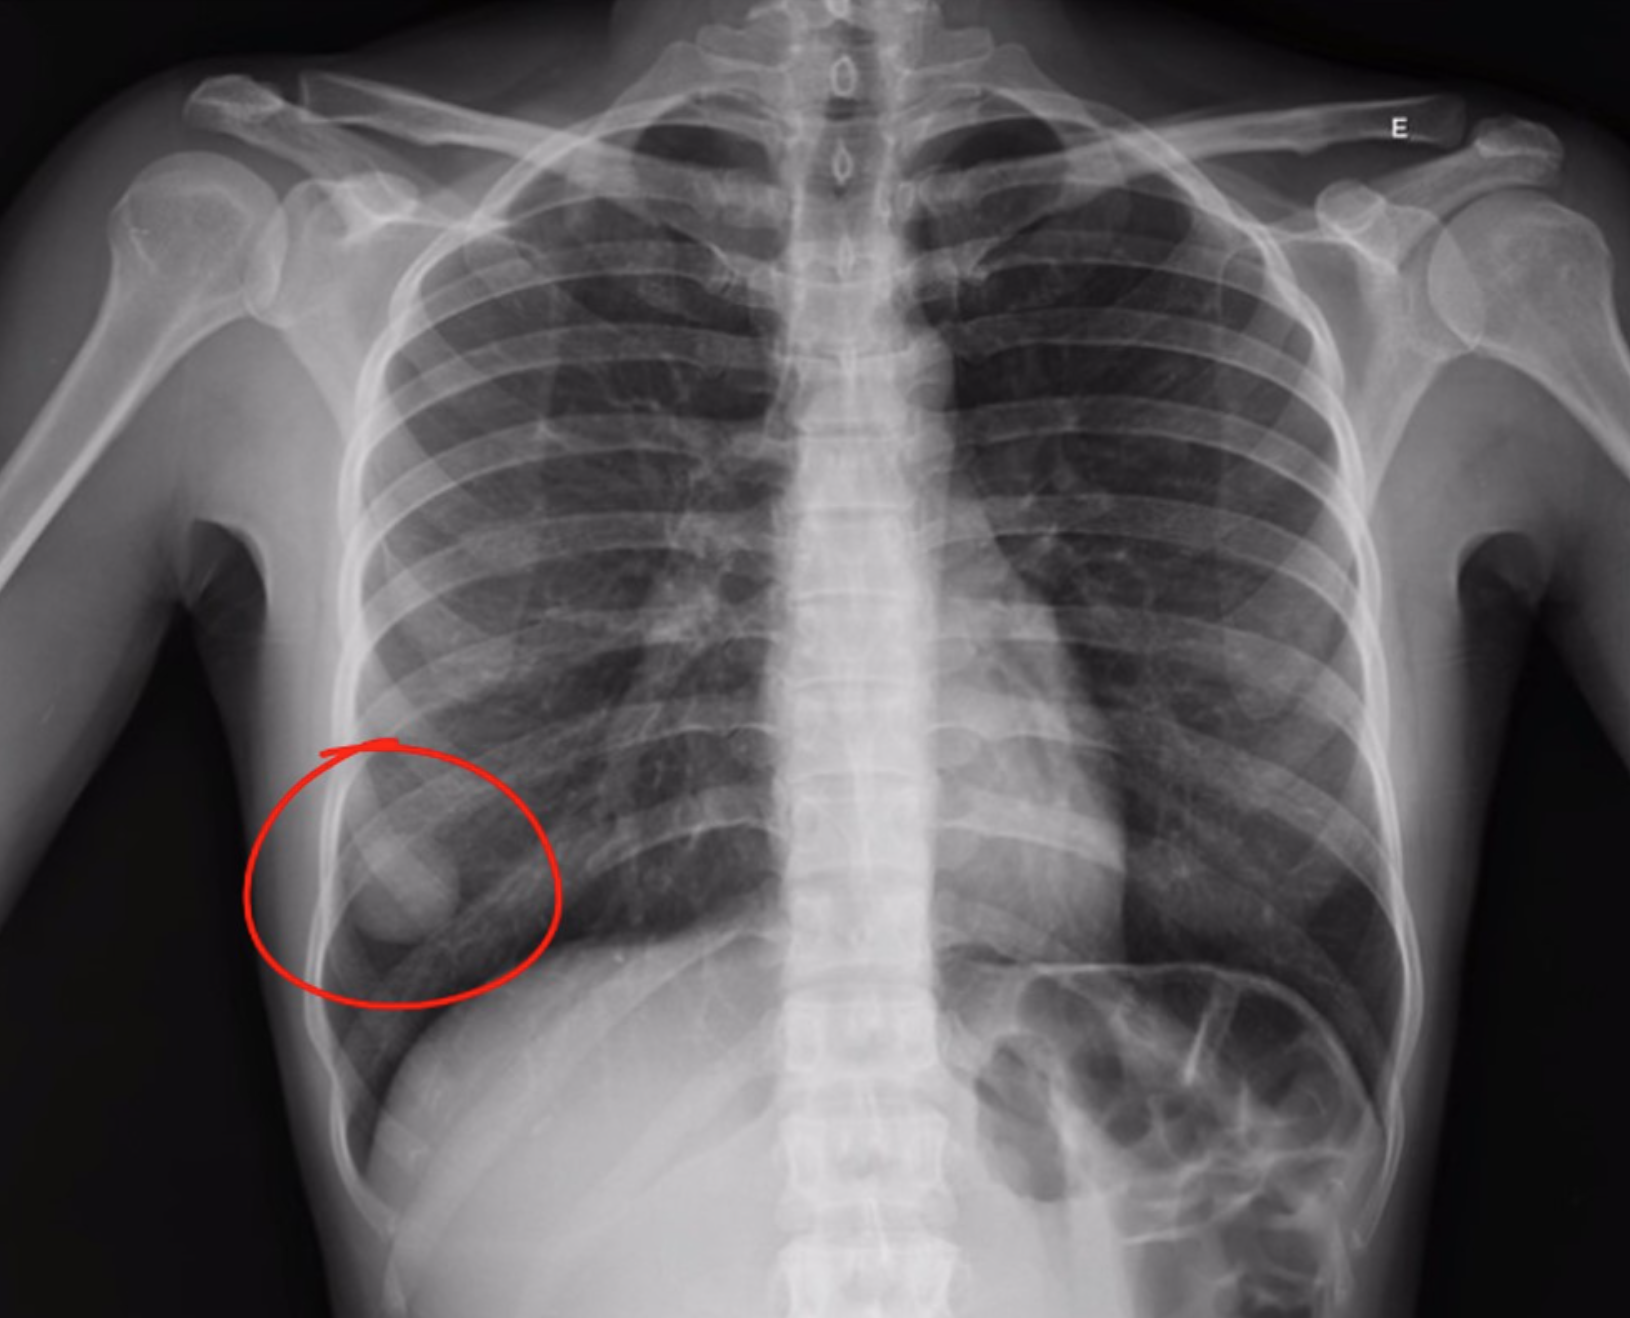

nodulo_RaioX_Torax

“Radiografia de tórax evidenciando nódulo pulmonar (círculo), um achado que pode ser identificado em exames simples e que frequentemente requer investigação complementar por tomografia.”